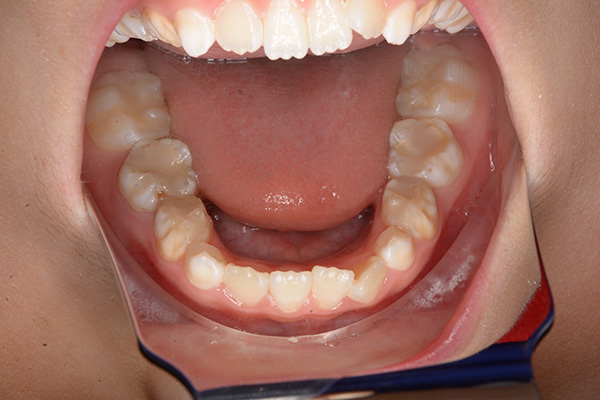

| 主訴 | 上顎前歯のでこぼこ | 診断名 | アングルⅡ級叢生症例 | ||||

|---|---|---|---|---|---|---|---|

| 初診時年齢 | 6歳9ヵ月 | 性別 | 男 | 動的治療期間 | 6ヵ月 | ||

| 既往歴として上顎正中過剰歯(2本)は抜去済み。その影響で上顎右側中切歯は捻転して萌出しており、下顎右側中切歯と早期接触が認められたため2x4(上顎のみブラケット装着)にて前歯部の改善を行った。現在は永久歯列完成まで経過観察を行い、希望があれば口元の突出感を改善するために本格矯正治療を行うことにしている。 | |